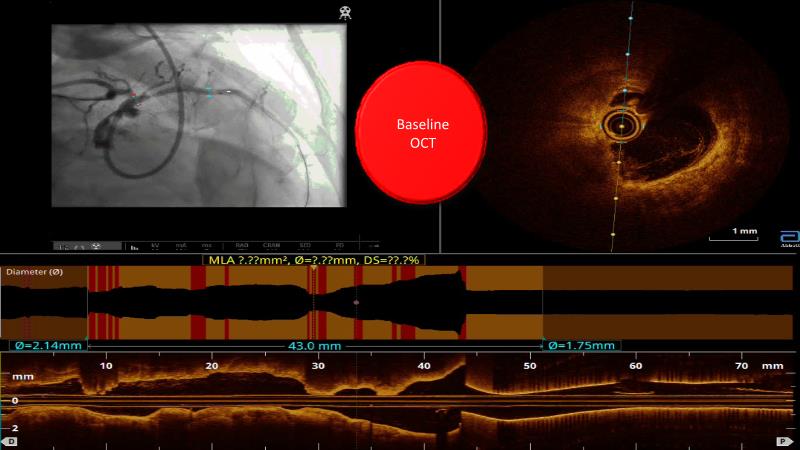

Watch this case-in-point presentation focusing on decision-making in complex PCI using OCT plus AI to understand how to take the right measurement throughout the procedure, how artificial intelligence aids in decision making during imaging-guided PCI, and to gain skills in interpreting OCT imaging, among others!

- To gain skill on OCT imaging interpretation

- To understand how to take the right measurement across the entire procedure